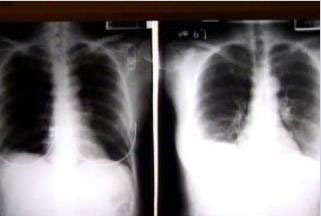

据台湾媒体报道,感染甲型H1N1流感重症的32岁男子,在医院住院治疗近一个月,期间曾一度并发多重器官衰竭,命在旦夕,所幸在体外循环机“叶克膜”的辅助下,病情已痊愈,目前是岛内首例,也是全球罕见案例。

这名年轻男子靠叶克膜救回痊愈引起医界关注,因为甲型流感病毒主要侵犯肺脏,引发严重病毒性肺炎,但这名男子心脏及肾脏却也同时衰竭,心跳一度停止、肾功能急速下降甚至需紧急洗肾,这样的病情机转,就连医界也还没找到确切原因。

台大心脏外科医师王植贤表示,叶克膜并无治疗作用,主要是协助支持心肺衰竭病患能暂时休养,藉由体外循环的作用让器官做自我修复,待一周后心肺功能回稳,就可以拆除叶克膜。而这名康复返家的病患肺脏有5成受损,但肺功能仍有希望持续进步,但叶克膜治疗痊愈的案例全球相当罕见。